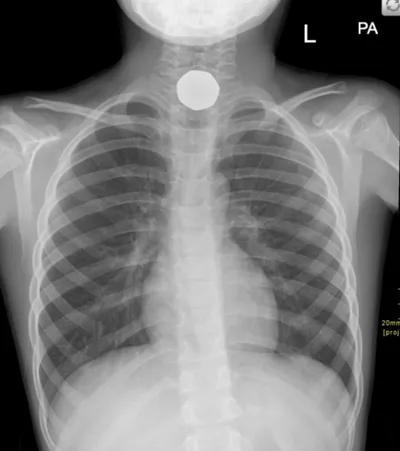

Esophageal Foreign Body Radiology Images

tagged: Esophageal Foreign Body

This collection contains 1 radiology images related to esophageal foreign body, including various imaging modalities such as X-rays, MRIs, CT scans, and ultrasound images commonly used in medical diagnosis and education.